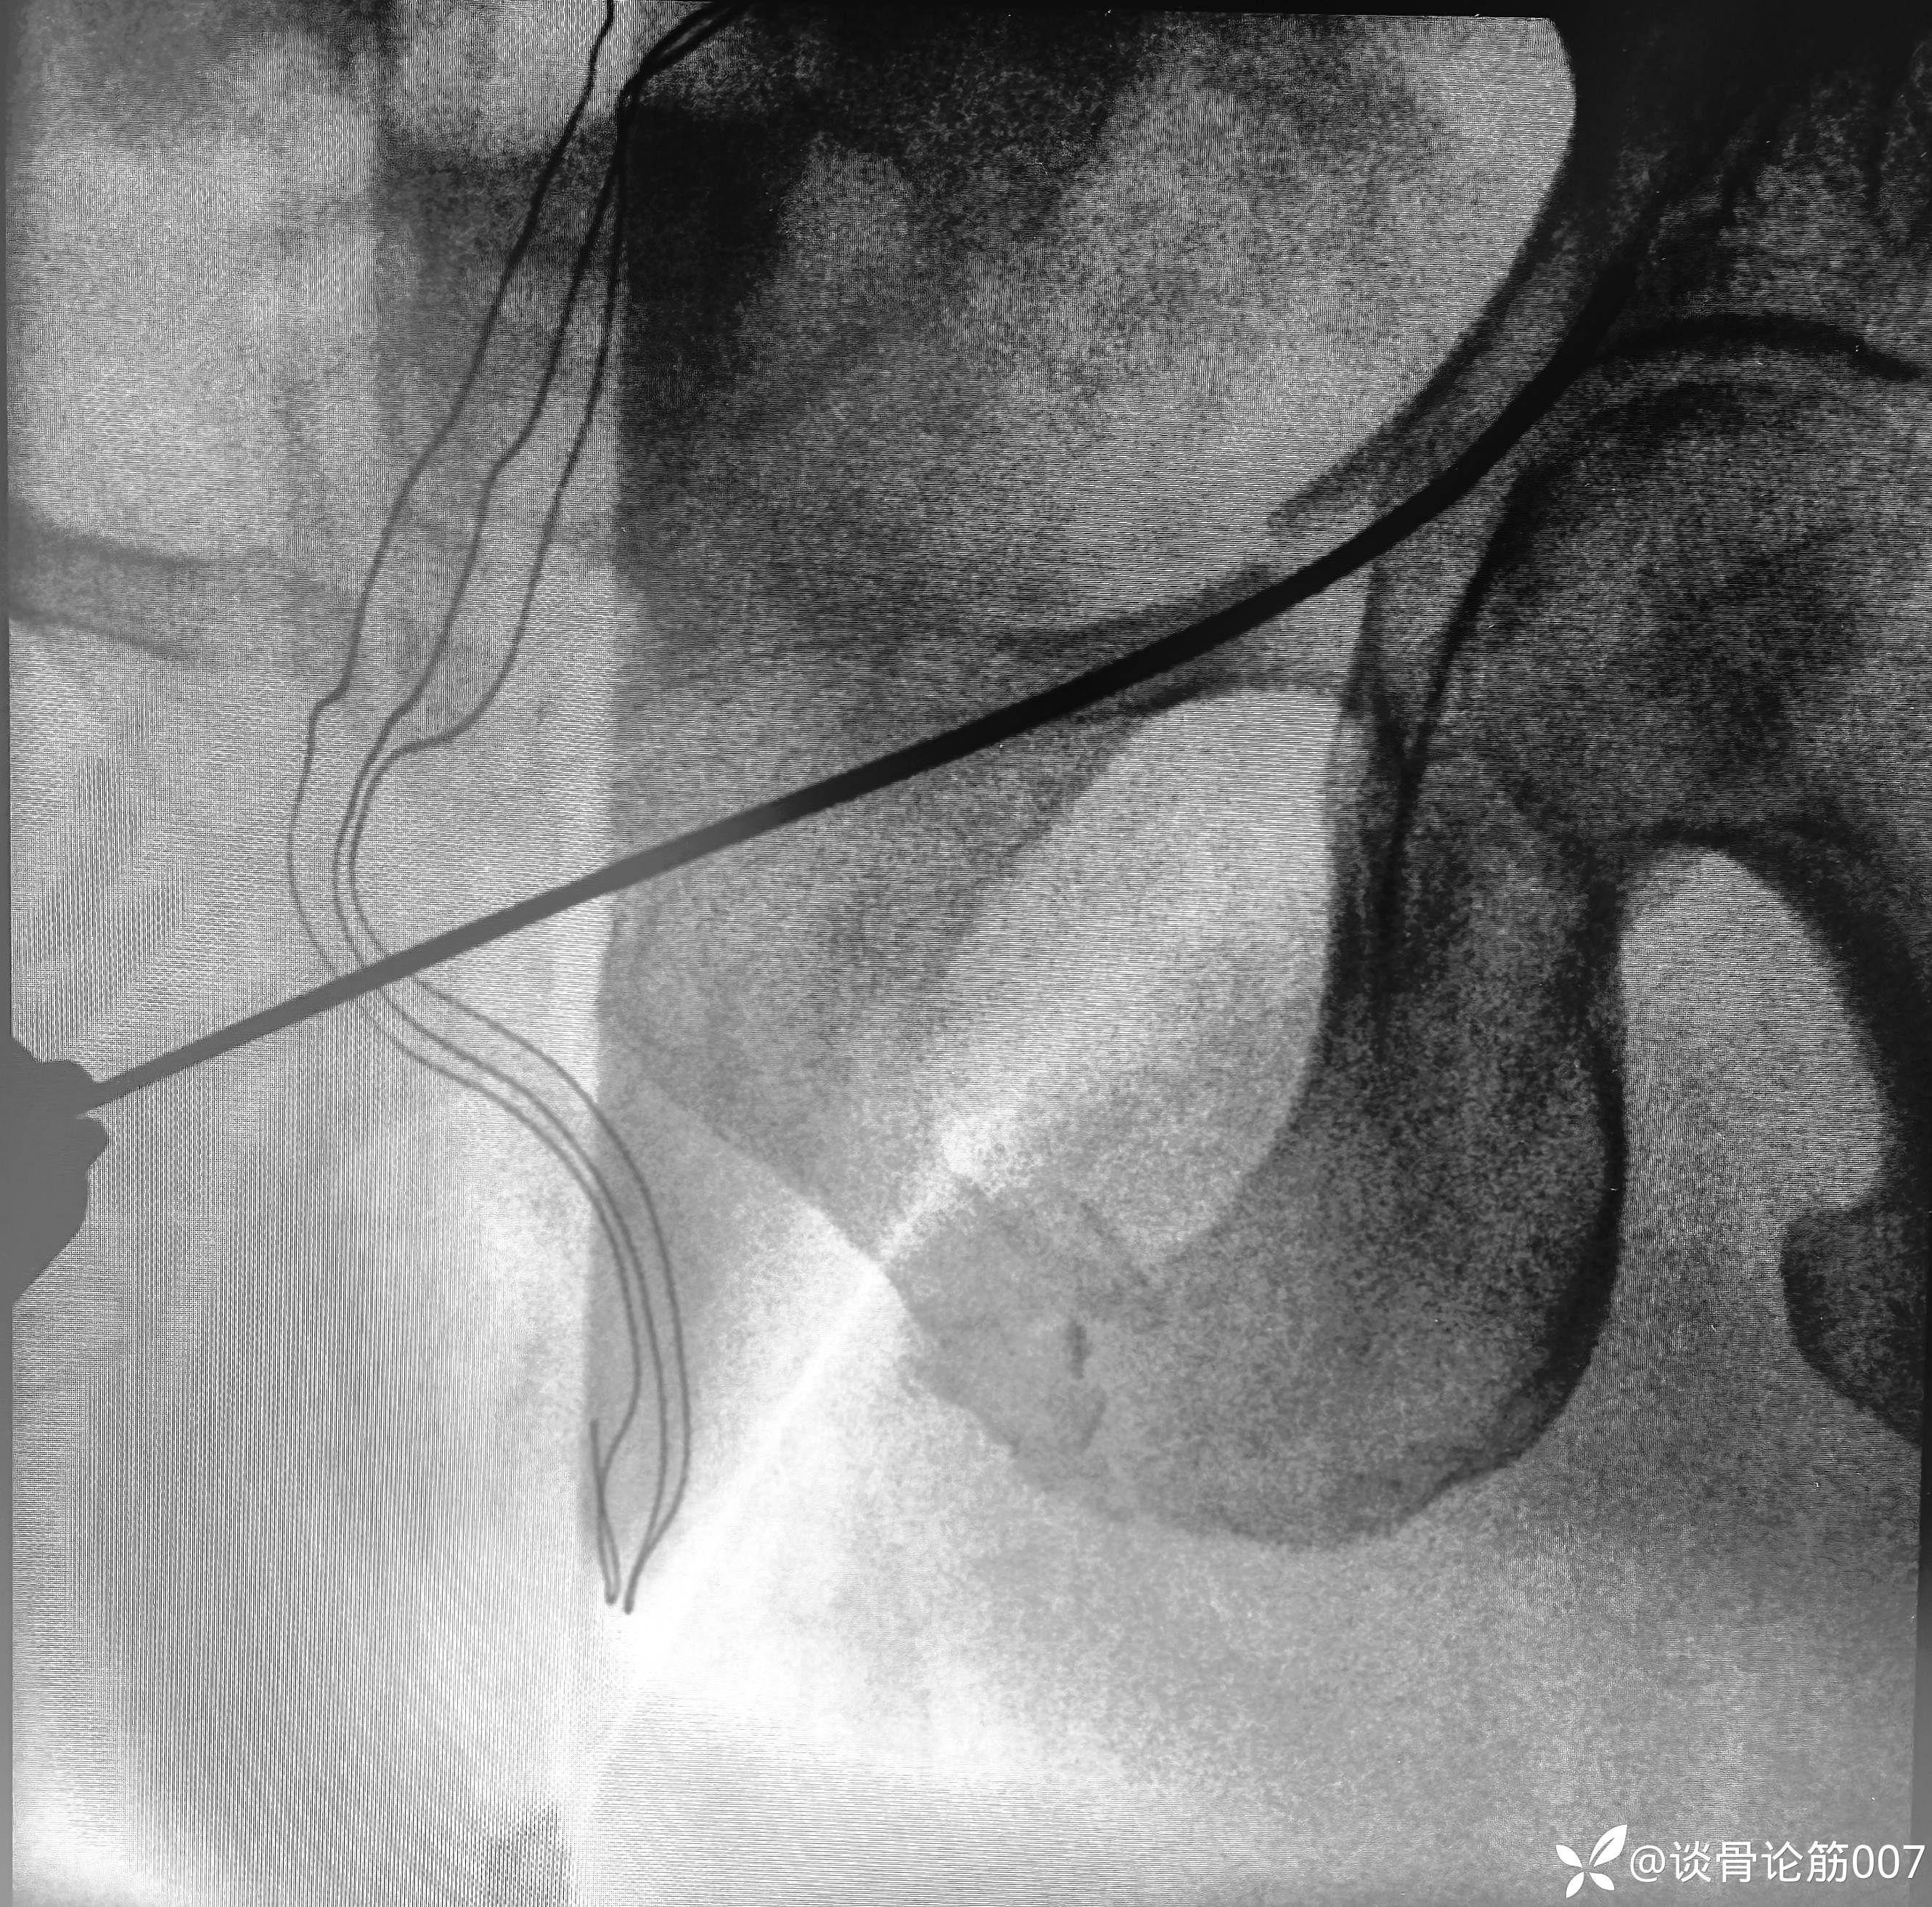

应用蛇钉技术避开髋臼

钉道方向还是有点差强人意